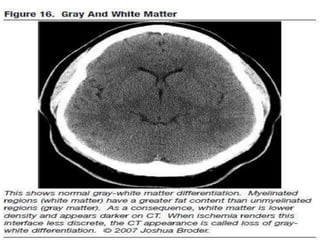

Grey and white matter differentiation

• Normally Grey matter is outer denser

structure and white matter in inner

hypodenser.

• Grey matter contains neurons cell bodies

while white matter contain axons with rich

fatty myelin sheath making it hypodense.

• This differentiation is loss in case of cerebral

odema.

Normal Grey white matter

Grey and whitematter differentiation • Normally Grey matter is outer denser structure and white matter in inner hypodenser. • Grey matter contains neurons cell bodies while white matter contain axons with rich fatty myelin sheath making it hypodense. • This differentiation is loss in case of cerebral odema.